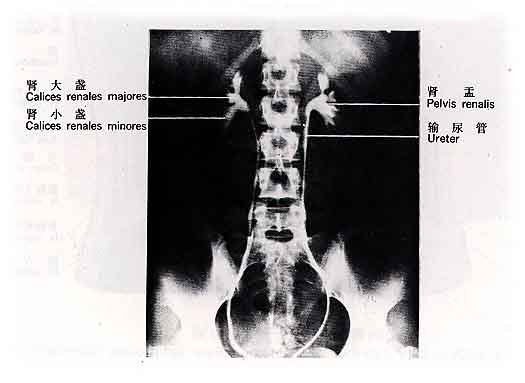

肾呈蚕豆形,分上下端,内外缘,前后面。内侧缘中部有血管、淋巴管、神经和肾盂出入称肾门。出入肾门的结构合称肾蒂。由肾门向肾内续于肾窦。窦内有肾动脉、肾静脉、肾小盏、肾大盏。肾小盏呈漏斗状,紧紧包绕着肾乳头,一个肾小盏包绕着1个或2个肾乳头,每2-3个小盏集合成肾大盏,大盏2-3个最后合并形成漏斗形的肾盂,出肾门后续于输尿管。